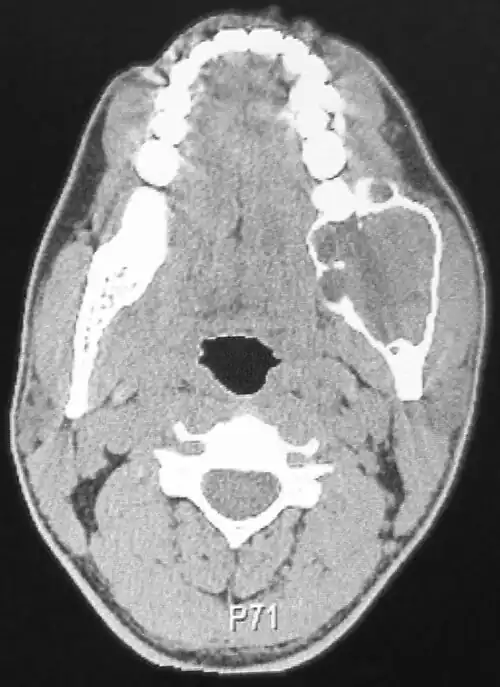

Das Ameloblastom ist meist ein Zufallsbefund, der als schmerzlose Kieferauftreibung imponiert. Etwa 30 % der Ameloblastome gehen von follikulären Zysten aus. In späteren Stadien kann es durch Resorptionsvorgänge die Zahnstellung verändern und durch Verlagerung und Druck auf Nerven Sensibilitätsstörungen hervorrufen. Es findet sich im Unterkiefer (bevorzugte Stellen: Kieferwinkel und aufsteigender Unterkieferast) sechsmal häufiger als im Oberkiefer (Eckzahnregion). Betroffen sind meist jüngere Patienten (30.–40. Lebensjahr), wobei die Verteilung bei Männern und Frauen etwa gleich hoch ist.

Im Röntgenbild zeigt sich eine ein- (seifenblasenartig) oder mehrkammrige (honigwabenartig), durch Knochenauflösungen (Osteolysen) scharf begrenzte Aufhellung mit Auflösung der Kortikalis.